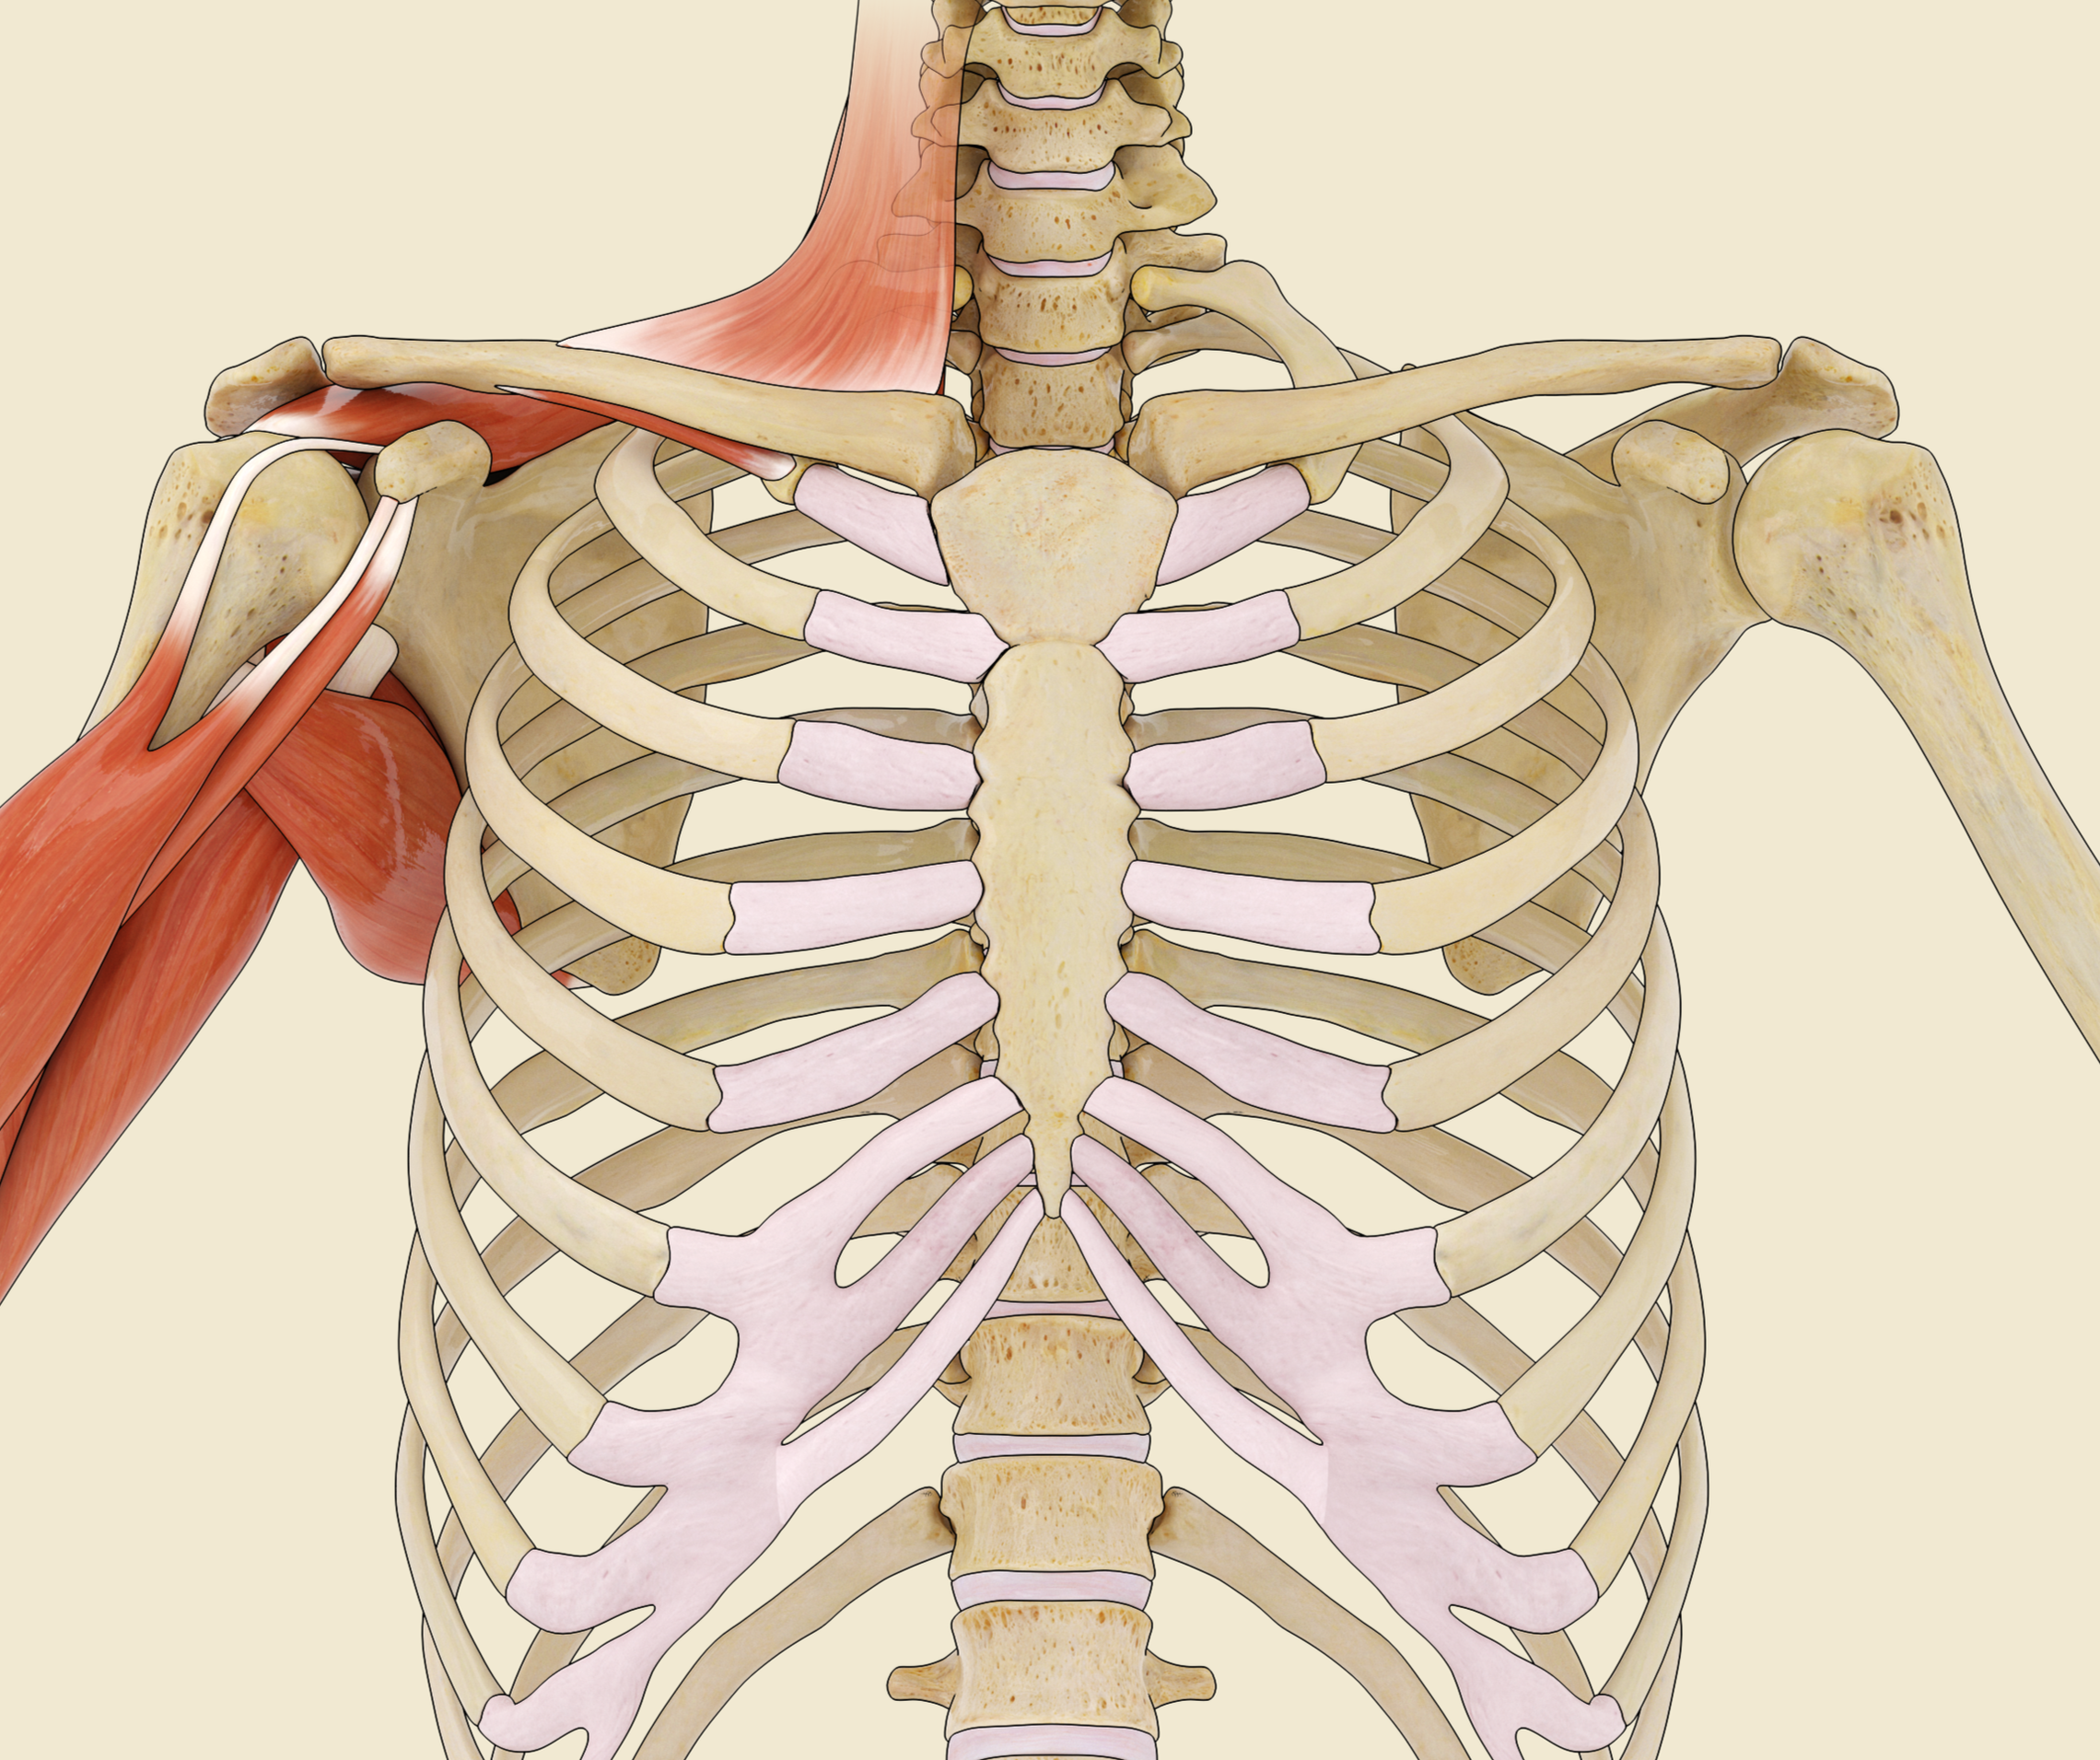

Medical and Scientific Illustration

Our team specializes in the creation of accurate, detailed medical and scientific illustrations designed to support demonstrative evidence in both prosecution and defense cases. We translate complex medical information into visuals that are precise, comprehensible, and persuasive — helping attorneys, expert witnesses, and juries clearly understand the facts of a case.

With expertise in human anatomy, physiology, pathology, and emergency medicine, our illustrators ensure every image meets the highest standards of scientific accuracy and visual clarity. Whether depicting surgical procedures, mechanisms of injury, or disease progression, we craft each illustration to communicate the truth with impact and precision.